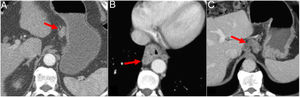

The formation of fistulas between the oesophagus and the trachea, bronchus or lung occurs in 5 %–10 % of cases of advanced OC. The risk increases in the case of previous radiotherapy. A fistula should be suspected in any patient with recurrent pneumonia. A diagnosis can be made by an oesophagram, and CT will show the fistulous tract23 (Fig. 5d). Oesophageal-pleural fistula is commonly associated with advanced OC. A chest X-ray may show air in the pleura or hydropneumothorax. CT is the test of choice for its diagnosis. Aorto-oesophageal fistula has also been described as an uncommon complication of tumour progression25 (Fig. 9).

Complication of advanced oesophageal cancer. A and A') Computed tomography (CT) images showing cT3N1M1a squamous cell carcinoma of the middle thoracic oesophagus; primary tumour (arrow) and mediastinal lymphadenopathy (arrow head). B and B') Post-neoadjuvant therapy CT: partial tumour response and fistulisation between tumour and lymphadenopathy (arrow head). C and C') CT 10 days later with aortoesophageal fistula: perforation of the oesophagus with extraluminal gas bubbles (arrow head) and active bleeding (arrow).